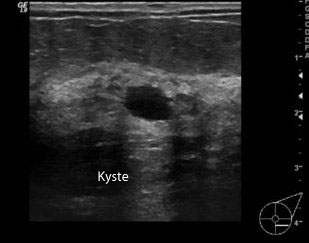

Elle précise donc une masse détectée en mammographie qui peut être liquide: kystique, solide: fibrome ou suspecte.